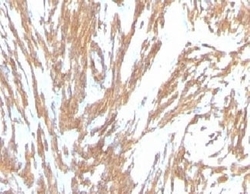

- Genetic validation

- Main image

- Experimental details

- Formalin-fixed, paraffin-embedded human Leiomyosarcoma stained with alpha Smooth Muscle Actin antibody (ACTA2/791). This image was taken for the unmodified form of this product. Other forms have not been tested.

- Genetic validation

- Main image

- Experimental details

- Formalin-fixed, paraffin-embedded human Leiomyosarcoma stained with alpha Smooth Muscle Actin antibody (ACTA2/791). This image was taken for the unmodified form of this product. Other forms have not been tested.